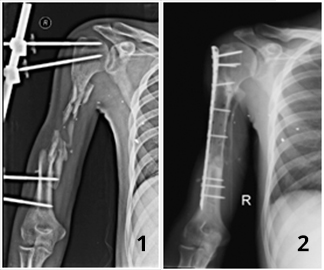

У парня в результате пулевого ранения образовался дефект правой плечевой кости на протяжении до 15 см. За помощью к нам обратился через 15 месяцев после ранения. До обращения проходил лечения в других лечебных учреждениях, где какой-либо помощи в восстановлении дефекта кости пациенту оказать не смогли.

Нами было проведено реконструктивно-восстановительное оперативное лечение с использованием клеточных технологий.

Через пол года в результате проводимого лечения целостность плечевой кости была восстановлена и пациент смог полноценно пользоваться конечностью.